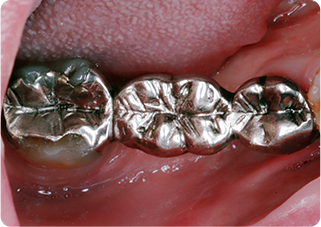

セラミックアンレー症例④

術前

インレー除去

ラバーダム防湿

シリコン印象

技工物

術後

| 主訴 | 右上奥歯の銀歯に食べ物が挟まる |

| 治療期間/回数 | 2週間、2回 |

| 価格(税込) | 77,000円(税込) |

| リスク・副作用 | セラミックの破損、一時的な知覚過敏が生じる場合がある |

| ポイント | 銀歯の詰め物の中がむし歯になっていたため、う蝕検知液を使用し選択的にむし歯のみを除去。またセラミック装着時にラバーダム防湿を行うことで、詰め物の接着効果を最大限発揮できるようにした。 |